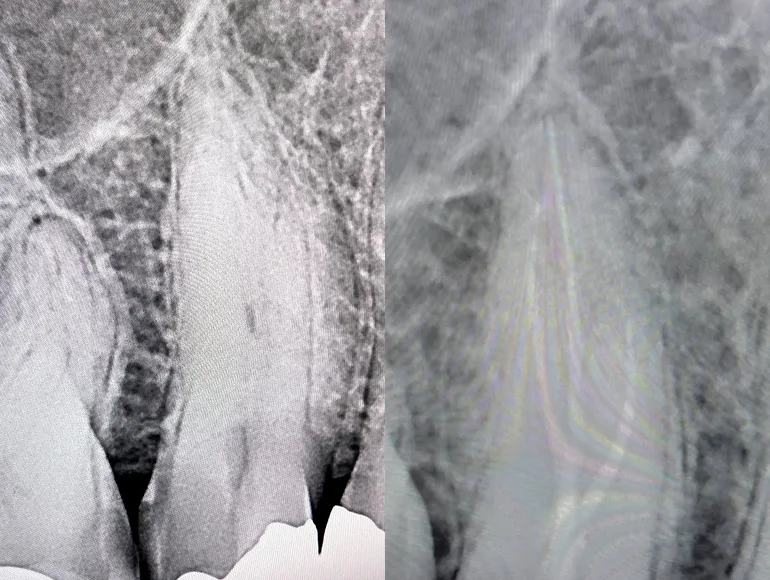

Retreatment of Rootcanal

Case by Dr. Taha Azimaie: Retreatment of failed rootcanal can give a patient another chance to retain the tooth. Retreatment is case selective and not all failed rootcanals are treatable. In this case root canal has failed due to poor sealing of the canals (The white lines in the roots) during the first treatment. Please note the sharp deviation of the canal at the tip of the root (the white line)